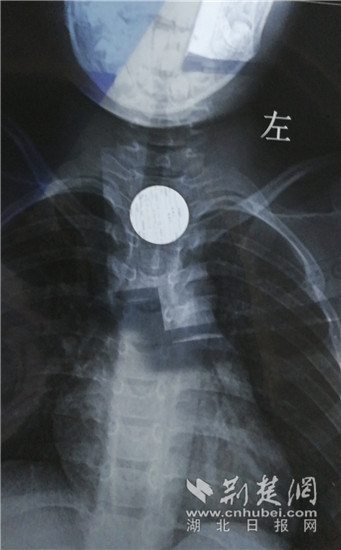

胸片显示硬币卡在食管上段。 (通讯员供图)

当地医院拍胸片发现,硬币卡在了食管上段,由于孩子太小,取出异物有风险,建议转到大医院救治。当晚爷爷奶奶带着亮亮在当地辗转多家医院,均被告知要等到第二天才能安排取出。看着亮亮痛苦不堪,不能讲话,无法吃喝,家人多方打听后连夜驱车,从洪湖赶到了武汉市第六医院。